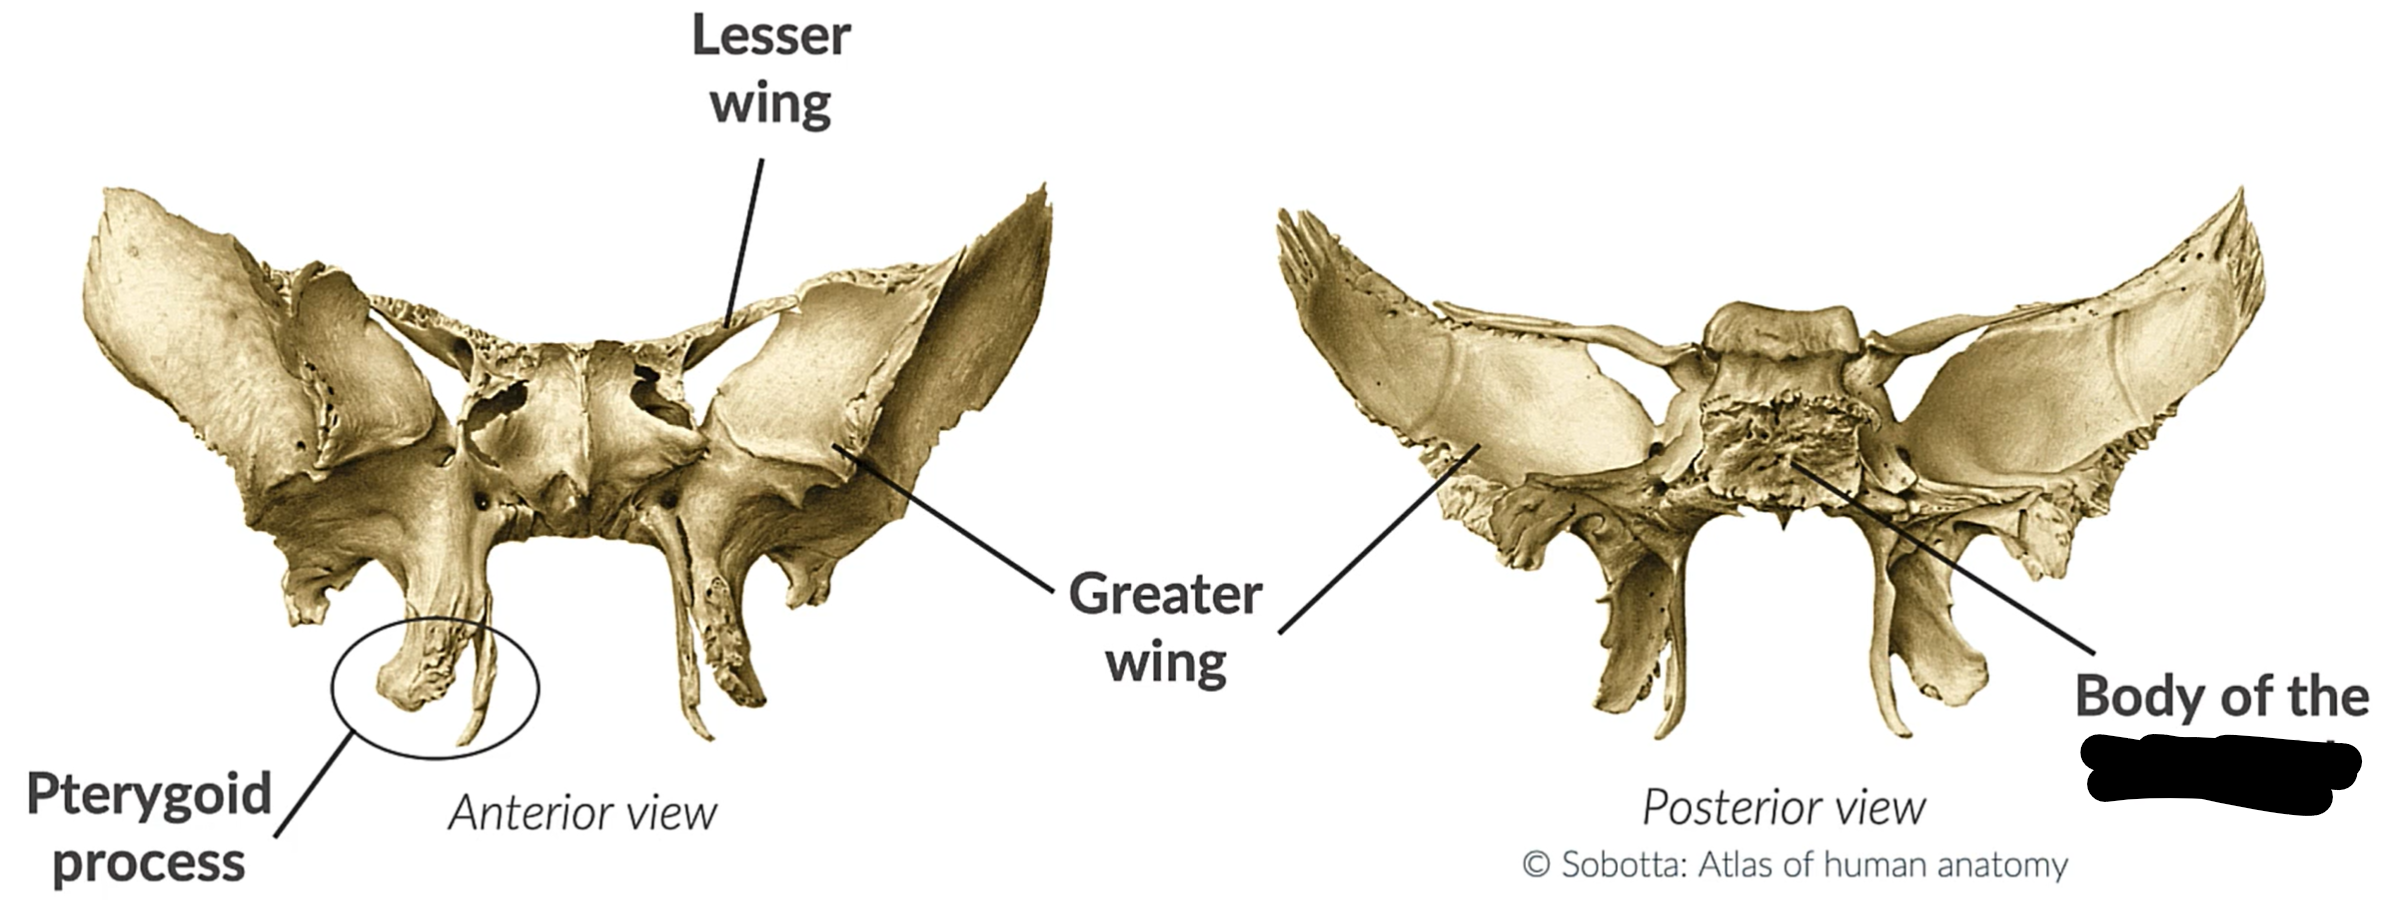

What bone is this?

Sphenoid bone

Lesser wing

Greater wing

Pterygoid process

Body sphenoid bone